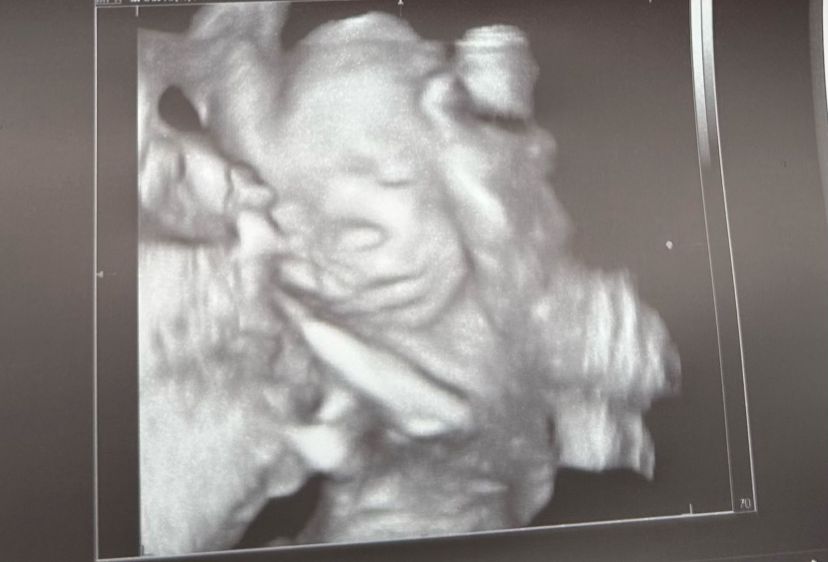

26-34 Weeks

This is the scan where you will be able to see your baby’s face as it will look like at birth. The best time to do this scan is between 30-32 weeks. In this period your baby’s facial features are fully formed and if baby is awake, you will even see different facial expressions. They might even open their eyes, and they often suck on a piece of cord, especially if you just had something to eat or drink and they like the taste.

The weight and wellbeing of your baby as well as surrounding structures like the placenta, amniotic fluid, cord and cervix will be included in our assessment.

Some of the 4D images are sent away for post processing to get an AI photo of what your baby may look like. This image is as close to a photograph of your baby that you can get. The ethnicity and gender is taken into account to optimise the image created.